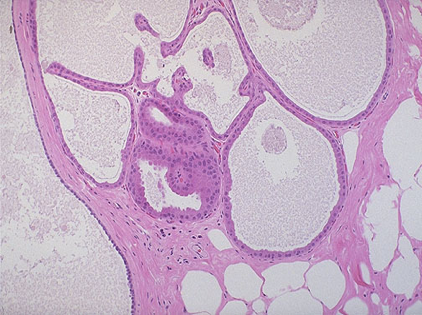

(一)乳腺纤维囊性变

乳腺纤维囊性变(fibrocystic changes)是最常见的乳腺疾患,多发于25岁-45岁之间的女性,绝经前达发病高峰,绝经后一般不再进展,极少在青春期前发病。发病多与卵巢内分泌失调有关,孕激素减少而雌激素分泌过多时,对此病的发生起一定的作用。

肉眼观,常为双侧,多灶小结节性分布,边界不清,囊肿大小不一,多少不等,相互聚集的小囊肿和增生的间质纤维组织相间交错,可产生斑驳不一的外观。大的囊肿因含有半透明的浑浊的液体,外表面呈蓝色,故称作蓝顶囊肿(blue-domed cysts)。

镜下,囊肿被覆的上皮可为柱状或立方上皮,但多数为扁平上皮,亦可上皮完全缺如,仅见纤维性囊壁。腔内偶见钙化。如囊肿破裂,内容物外溢进入周围的间质,可致炎症性反应和间质纤维组织增生,纤维化的间质进一步发生玻璃样变。

囊肿上皮常可见大汗腺化生(apocrine metaplasia),细胞体积较大,胞浆嗜酸性,细胞浆的顶部可见典型的顶浆分泌小突起,形态和大汗腺的上皮相似。